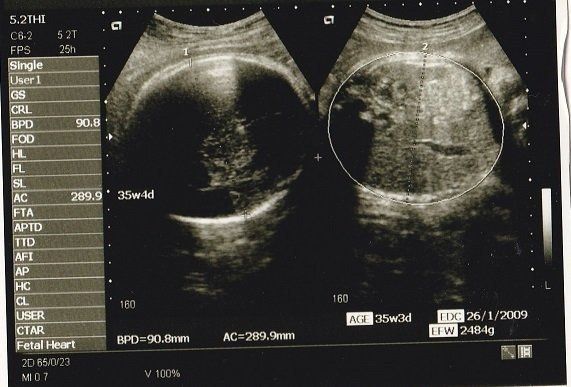

妊娠週 胎児の大きさや様子 妊娠週胎児体重は正常発育児の954%が 211g~416g 平均体重: 313g となります。 ※1 この時期の赤ちゃんは足もしっかり曲げたり伸ばしたりできるようになっています。 当初はかなり小さなサイズだった子宮もどんどん大きく エコーに写る位、髪の毛フッサフサだそうな(笑)。 — ひろっちゃん (@hiroto_yuzuki) 15 October 18 先輩ママ 髪の毛のことまでわかるのですね。 つかの間の帰省を終えて帰宅。 目は開けてみないと一重か二重かわからんけど、鼻と口は多分娘と同じ感じ。楽しみやなぁ — ゆっさん®︎ 4y&11m姉妹 超音波エコー写真妊娠中期(妊娠16週目~妊娠27週目) 妊娠中期(16週目~27週目)の超音波エコー写真を紹介します。 井上裕子先生 プロフィール 東京都立川市 井上レディスクリニック院長。 産婦人科専門医、日本乳癌学会認定医、認定健康スポーツ医 他。 診療のかたわら、

妊娠32週目 逆子は治る 胎児の体重や大きさをエコー写真で確認 妊娠後期 All About

妊娠24週目 エコー写真で見る胎児大きさと体重 早産になったら 妊娠中期 All About

妊娠9ヶ月 妊娠32週 33週 34週 35週 妊娠後期 の超音波写真 妊娠 出産 育児に関する総合情報サイト ベビカム

エコーの見方が分からないのですが このエコー写真には赤ちゃんの体重や身長 Yahoo 知恵袋